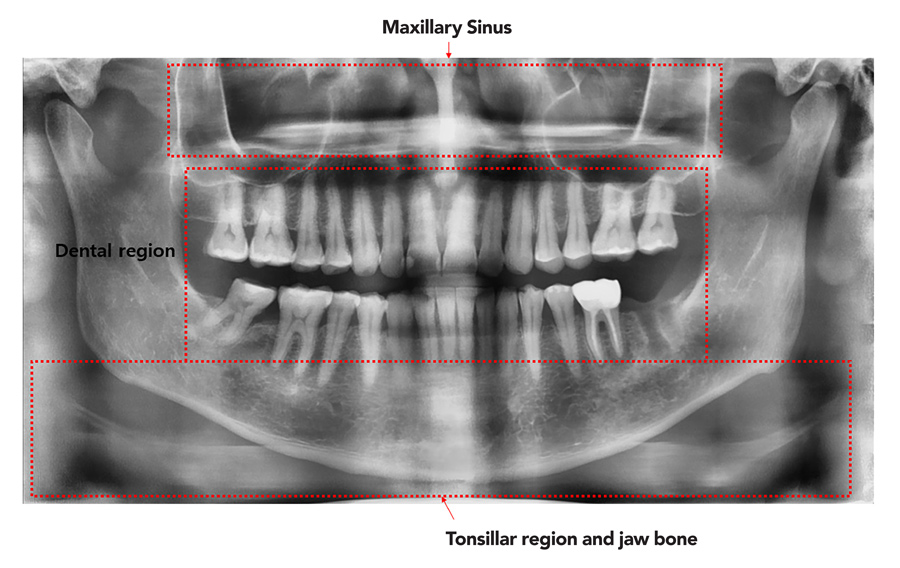

人工智能广泛用于牙科诊断正常和异常结构并诊断从临床例程收集的多部医学图像中采集的疾病全景口射线常用单一图像诊断牙病并计划后续治疗图片复杂 人工检验耗时费力除牙类异常外,从这些图像中获取的放射学发现可用于诊断系统性疾病,如分辨分辨和超分辨类固醇(异常低或高水平对血液中的钙水平有影响)和骨质疏松症(骨质疏松症)。因时间有限,牙科医生可能只专注于有症状的牙类,因此过滤健康图像的能力有助于诊断和省时

研究者解释前研究如何在牙医学中应用AI并成功检测定向口服疾病不过,它们只能瞄准少数异常信号或疾病模型使用卷积神经网络分类图像并检测对象但他们没有利用全景牙射线学关键利益,因为它将整口封装成单一图像包括上下巴、个人牙类和周围组织与结构此外,过滤健康图像会减少需要人工检验的图像数并减轻牙科医师的负担

Lee和他的合作者选择17个细度牙异常 从全景牙图片中检测使用现代AI计算机视觉技术开发模型,可用于临床实践检测异常大量高质量数据集对机器学习至关重要,因此研究队从30个本地牙疗所收集22 999全景牙图片,从2020年7月至2021年7月持续一年数据集中的每一图像均由牙科放射学专家人工检查并贴上标签,该专家注意到图像中存在的任何重要特征或异常